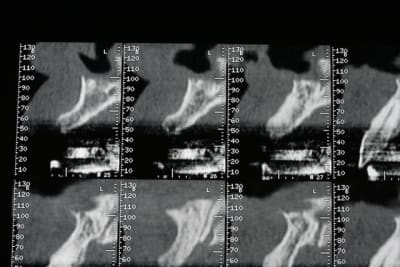

bon, première salve...

photos du scanner...et avec la planche radio pour bien estimer le volume disponible

d'entrée de jeu, on peut se dire que çà va être plus coton pour la 22 que pour la 12 car on à moins d'épaisseur et la corticale est plus dense...